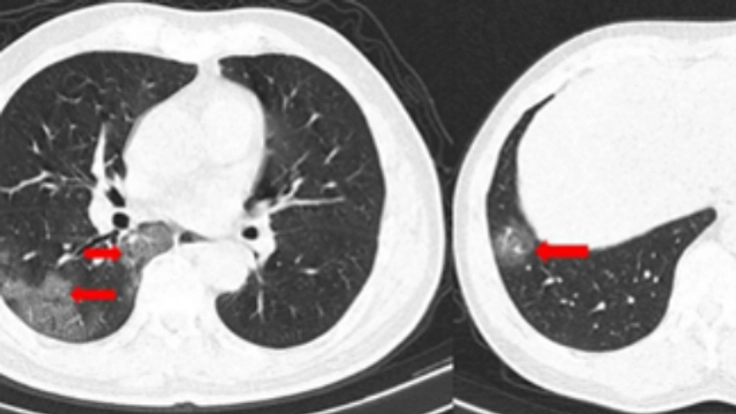

新型コロナウィルスによる肺炎を早期発見する為の低線量CT導入